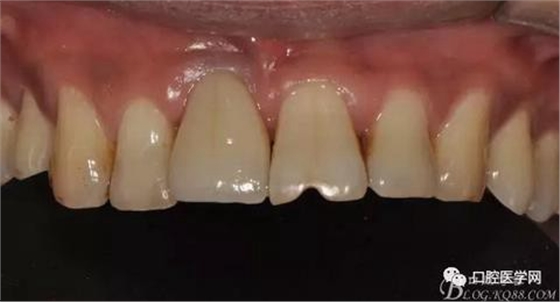

圖21 術(shù)后正位照

圖22 術(shù)后正位黑背板照

圖23 術(shù)后正位咬頜照